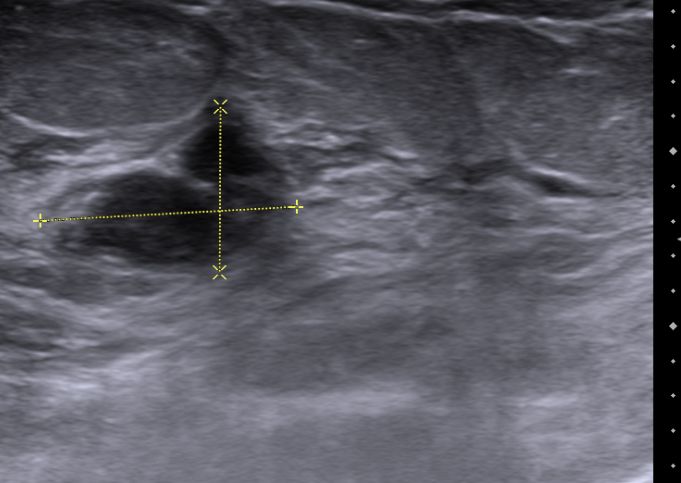

| Mammographie | 76-jährige Patientin mit multiplen Metastasen in Wirbelsäule und Leber. Zunächst kein Tastbefund der Brust. Dann suspekter Tastbefund rechts oben außen paramamillär. Mammographie zunächst o.B. befundet. Stanzbiopsie rechts oben außen: lobuläres Karzinom. | |||||||||